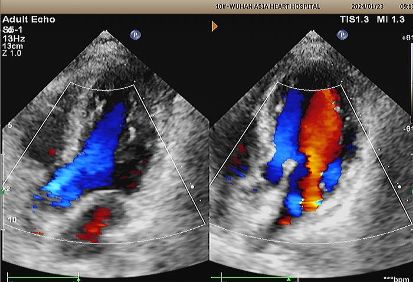

Écho d'une année:

No visible disc structures – replaced by 8mm tissue thickening at the septal implant site.

Zero residual shunt (rest or post-Valsalva).

Absorption complète de l'appareil confirmée.